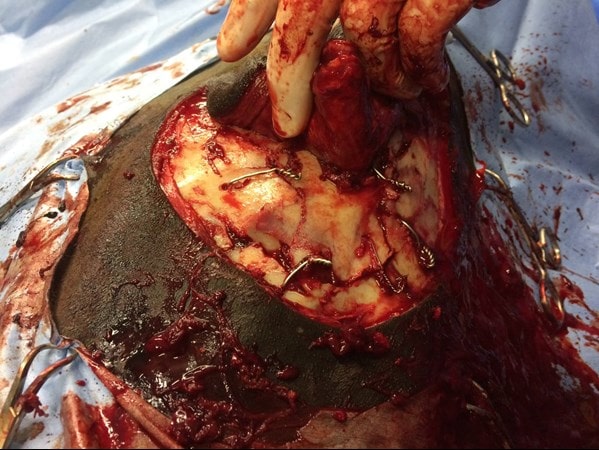

Some fragments were depressed to the extent that they were coursing vertically into the head, perpendicular to their normal position. The fractures extended around the dorsal margin of the orbit. The fragments were gradually levered back into their normal position but it also was clear that they would not be self-retaining and so adjacent fragments were secured to one another using stainless steel wire. One large central loose fragment was obscured by the tissue between the two incisions and so the incisions were connected rostrally.

This then allowed anatomical reconstruction using five wires in total. The orbit was largely reconstructed although a defect remained at the medial canthus through bone loss but the orbit contacting the globe was confirmed by palpation to be smooth. At the end of surgery, a more normal contour to the face could be appreciated. The prolapse of the third eyelid had also resolved. Because of the severity of the corneal ulceration and the delicacy of the area around the eye, a subpalpebral lavage system was placed to allow remote medication of the eye.